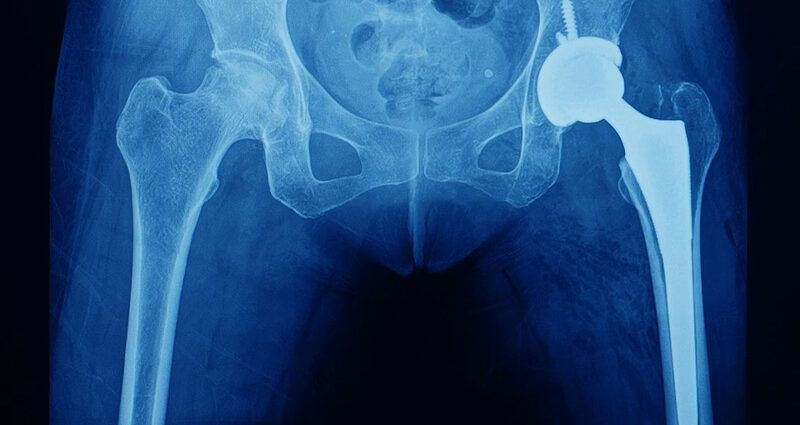

In principle, hip replacement surgery is the same operation no matter your age. But there are some slight variations.

In patients aged 70 and older, the prosthesis components are usually glued to fix them to the bone, commonly called a cemented hip. The moving parts are typically made of metal and plastic.

But in younger people, the surgeon may use implants that rely on bone growing onto the surface to fix the replacement joint in place – commonly called a cementless (or uncemented) hip. The moving part of the joint will also be separate to the part that fixes onto the bone. This means they can easily be changed if they become very worn over the years without having to change the whole joint replacement.

In younger people, the moving parts may also be made of different materials – such as ceramic, as it’s more hard-wearing than metal.